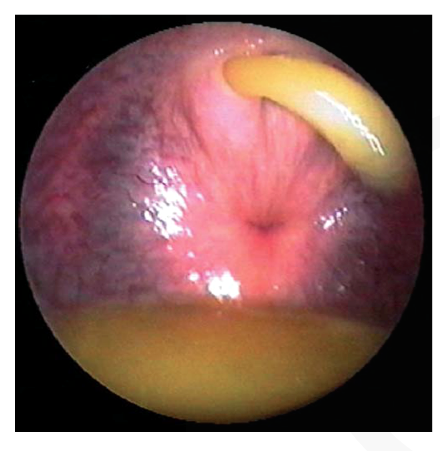

prostrate gland